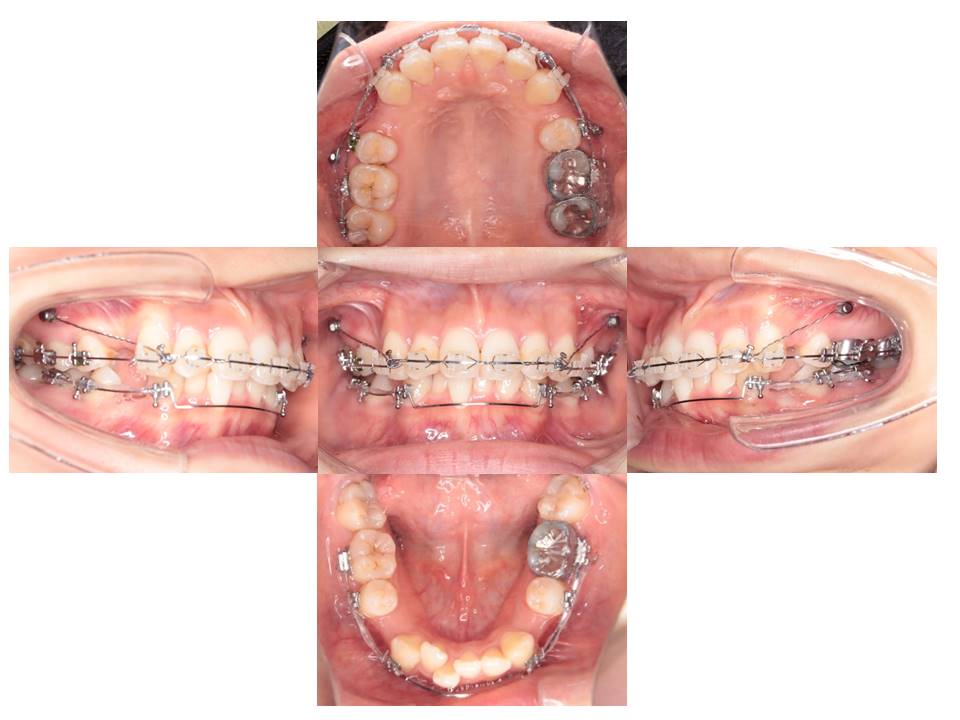

上あごと下あごの歯を並べています。